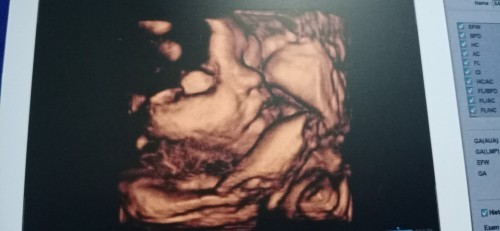

32+4วีค แล้วคับผม

บ้านนี้เพศชาย กำหนดคลอด20ตุลา แม่ๆบ้านอื่นคลอดเดือนไหน เห็นเพศกันรึยังคะ❤❤❤#ท้องแรกคะ